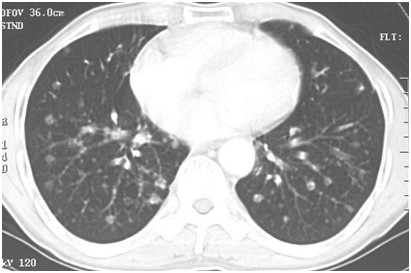

02卷-3.男性,55歲,結(jié)腸癌術(shù)后2年。(本題滿分2.00分)

D.肺轉(zhuǎn)移癌

本題答案:D

題目解析:

【該題針對(duì)“ X線-肺癌 ”知識(shí)點(diǎn)進(jìn)行考核】